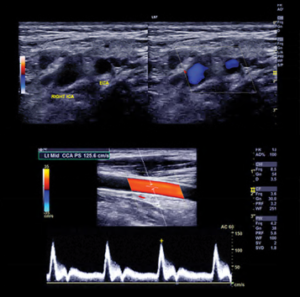

Carotid Duplex Ultrasonography

Michael R. Jaff, DO, FACP, FACC